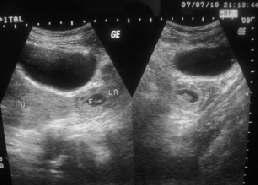

Ararecaseofrecurrent(consecutive)ectopicpregnancywithfibroiduterus

— Owvass Hamied Dar, Maqsood Ahmad Dar, Ghanshyam, Pankaj Sharma ....................................72